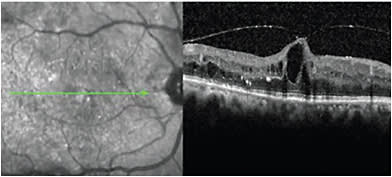

DME can have a tractional component caused by a thickened and taut posterior hyaloid (Figures 3 and 4) clinically identified by the increased glistening of the paramacular vitreous face). Initially advocated for clearing of media opacities and relief of retinal traction, vitrectomy techniques have advanced, leading to more complex indications for the treatment of DME.12,13 Vitrectomy facilitates greater blood flow through retinal vessels, and it has also been reported to improve retinal oxygenation 10 times more than in non-vitrectomized eyes.14 A review of previous findings shows that vitrectomy is effective at reducing retinal thickness in some cases of chronic DME.15 However, vision fails to improve in many of these patients. The reason may be that only recalcitrant DME cases—such as those with permanent outer retinal damage—that have failed other therapies are undergoing vitrectomy. In many of these studies, investigators did not employ optical coherence tomography (OCT) when evaluating their DME patients.